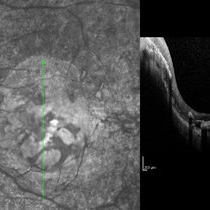

Choroidal Osteoma  + CNV Choroidal Osteoma  + CNVMar 13 2013 by Hamid Ahmadieh, MD Optical coherence tomography (OCT) of the right eye of a 13-year-old girl with decreased VA due to CNV secondary to choroidal osteoma. Photographer: Naghmeh Nozhat, Negah Eye Center, Tehran Imaging device: Topcon Condition/keywords: choroidal neovascularization (CNV), choroidal osteoma, optical coherence tomography (OCT)